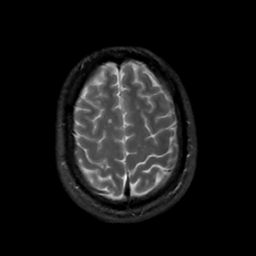

MR Study #2, February 17, 1991 -- Slice #41

[Home][Help][Clinical][Tour 1][Tour 2] Slice 41